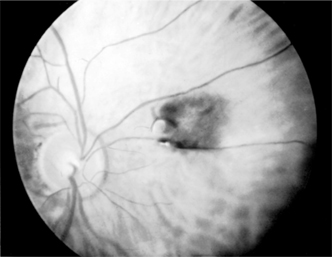

1. OCULAR TOXOPLASMOSIS

Toxoplasmosis is caused by Toxoplasma gondii, an obligate intracellular protozoan (Figure 7-5). The ocular lesions may be acquired in utero or following systemic infection. Constitutional symptoms may be mild and easily missed. The domestic cat and other feline species serve as definitive hosts for the parasite. Susceptible women who acquire the disease during pregnancy may transmit the infection to the fetus, where it can be fatal. Sources of human infection include oocysts in soil or airborne in dust, undercooked meat containing bradyzoites (encysted forms of the parasite), and tachyzoites (proliferative form) transmitted across the placenta.

Figure 7-5

Figure 7-5: Toxoplasma cysts in the retina. (Courtesy of K Tabbara.)

Clinical Findings (Figure 7-5)

A. Symptoms and Signs:

Patients with toxoplasmic retinochoroiditis present with a history of floaters and blurred vision. In severe cases there may also be pain and photophobia. The ocular lesions consist of fluffy-white areas of focal necrotic retinochoroiditis that may be small or large and single or multiple. Active edematous lesions are often adjacent to healed retinal scars. Retinal vasculitis and hemorrhage can be observed. Cystoid macular edema can accompany lesions in or near the macula. Iridocyclitis is frequently seen in patients with severe infections, and intraocular pressure may be elevated.